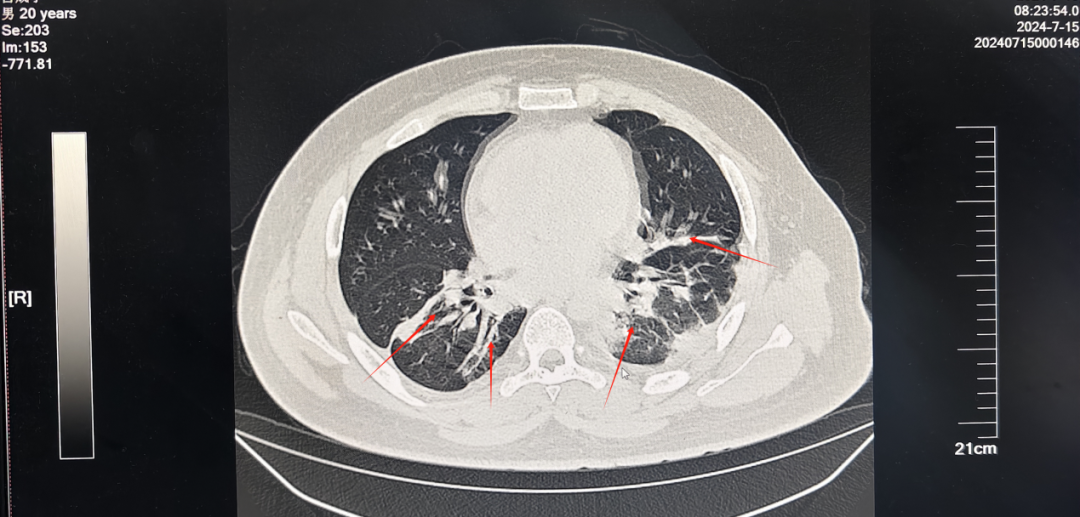

血液净化是清除患者体内毒物的唯一方法也是唯一希望。在救治团队精准治疗方案下,毒物监测提示病人体内毒物含量逐步下降。7月15日,患者血清百草枯定量已经小于20ug/L,肝肾脏器功能损伤得到明显控制。

然而,患者双肺损伤不容乐观,胸部CT显示在胸腔积液的基础上,部分出现纤维化。

治疗4周后,胸部CT检查显示,患者双肺损伤无再进展,反而渗出得到了吸收,左侧胸腔积液明显减少,至此,中毒得到有效控制,医护人员与患者共同鏖战29天,迎来了“重生”。